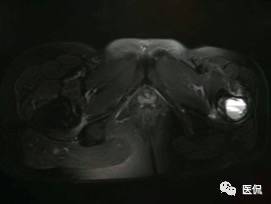

患者资料:男,26岁,左髋部疼痛10余天,无明显诱因出现左侧髋部疼痛,影像行走,夜间疼痛尤其明显。

影像资料:

(3)MRI ABC的特征为鼓囊状的膨胀性破坏,呈单囊或由低信号的间隔分隔成大小不等的多囊。因血细胞和血浆的分离和沉淀,囊内可见液-液平面。在T2WI上,液面上层为高信号,下层为低信号;T1WI上则相反,上层为低信号,下层为偏高信号。液-液平面是ABC较特征的征象。增强检查低信号的纤维间隔呈环形强化。继发性动脉瘤样骨囊肿可在其原发病灶内有液-液平。

【诊断要点】发生于青少年长骨干骺端偏心膨胀的溶骨性病变,MRI检查病灶内见有液-液平征象时应首先考虑为动脉瘤样骨囊肿。